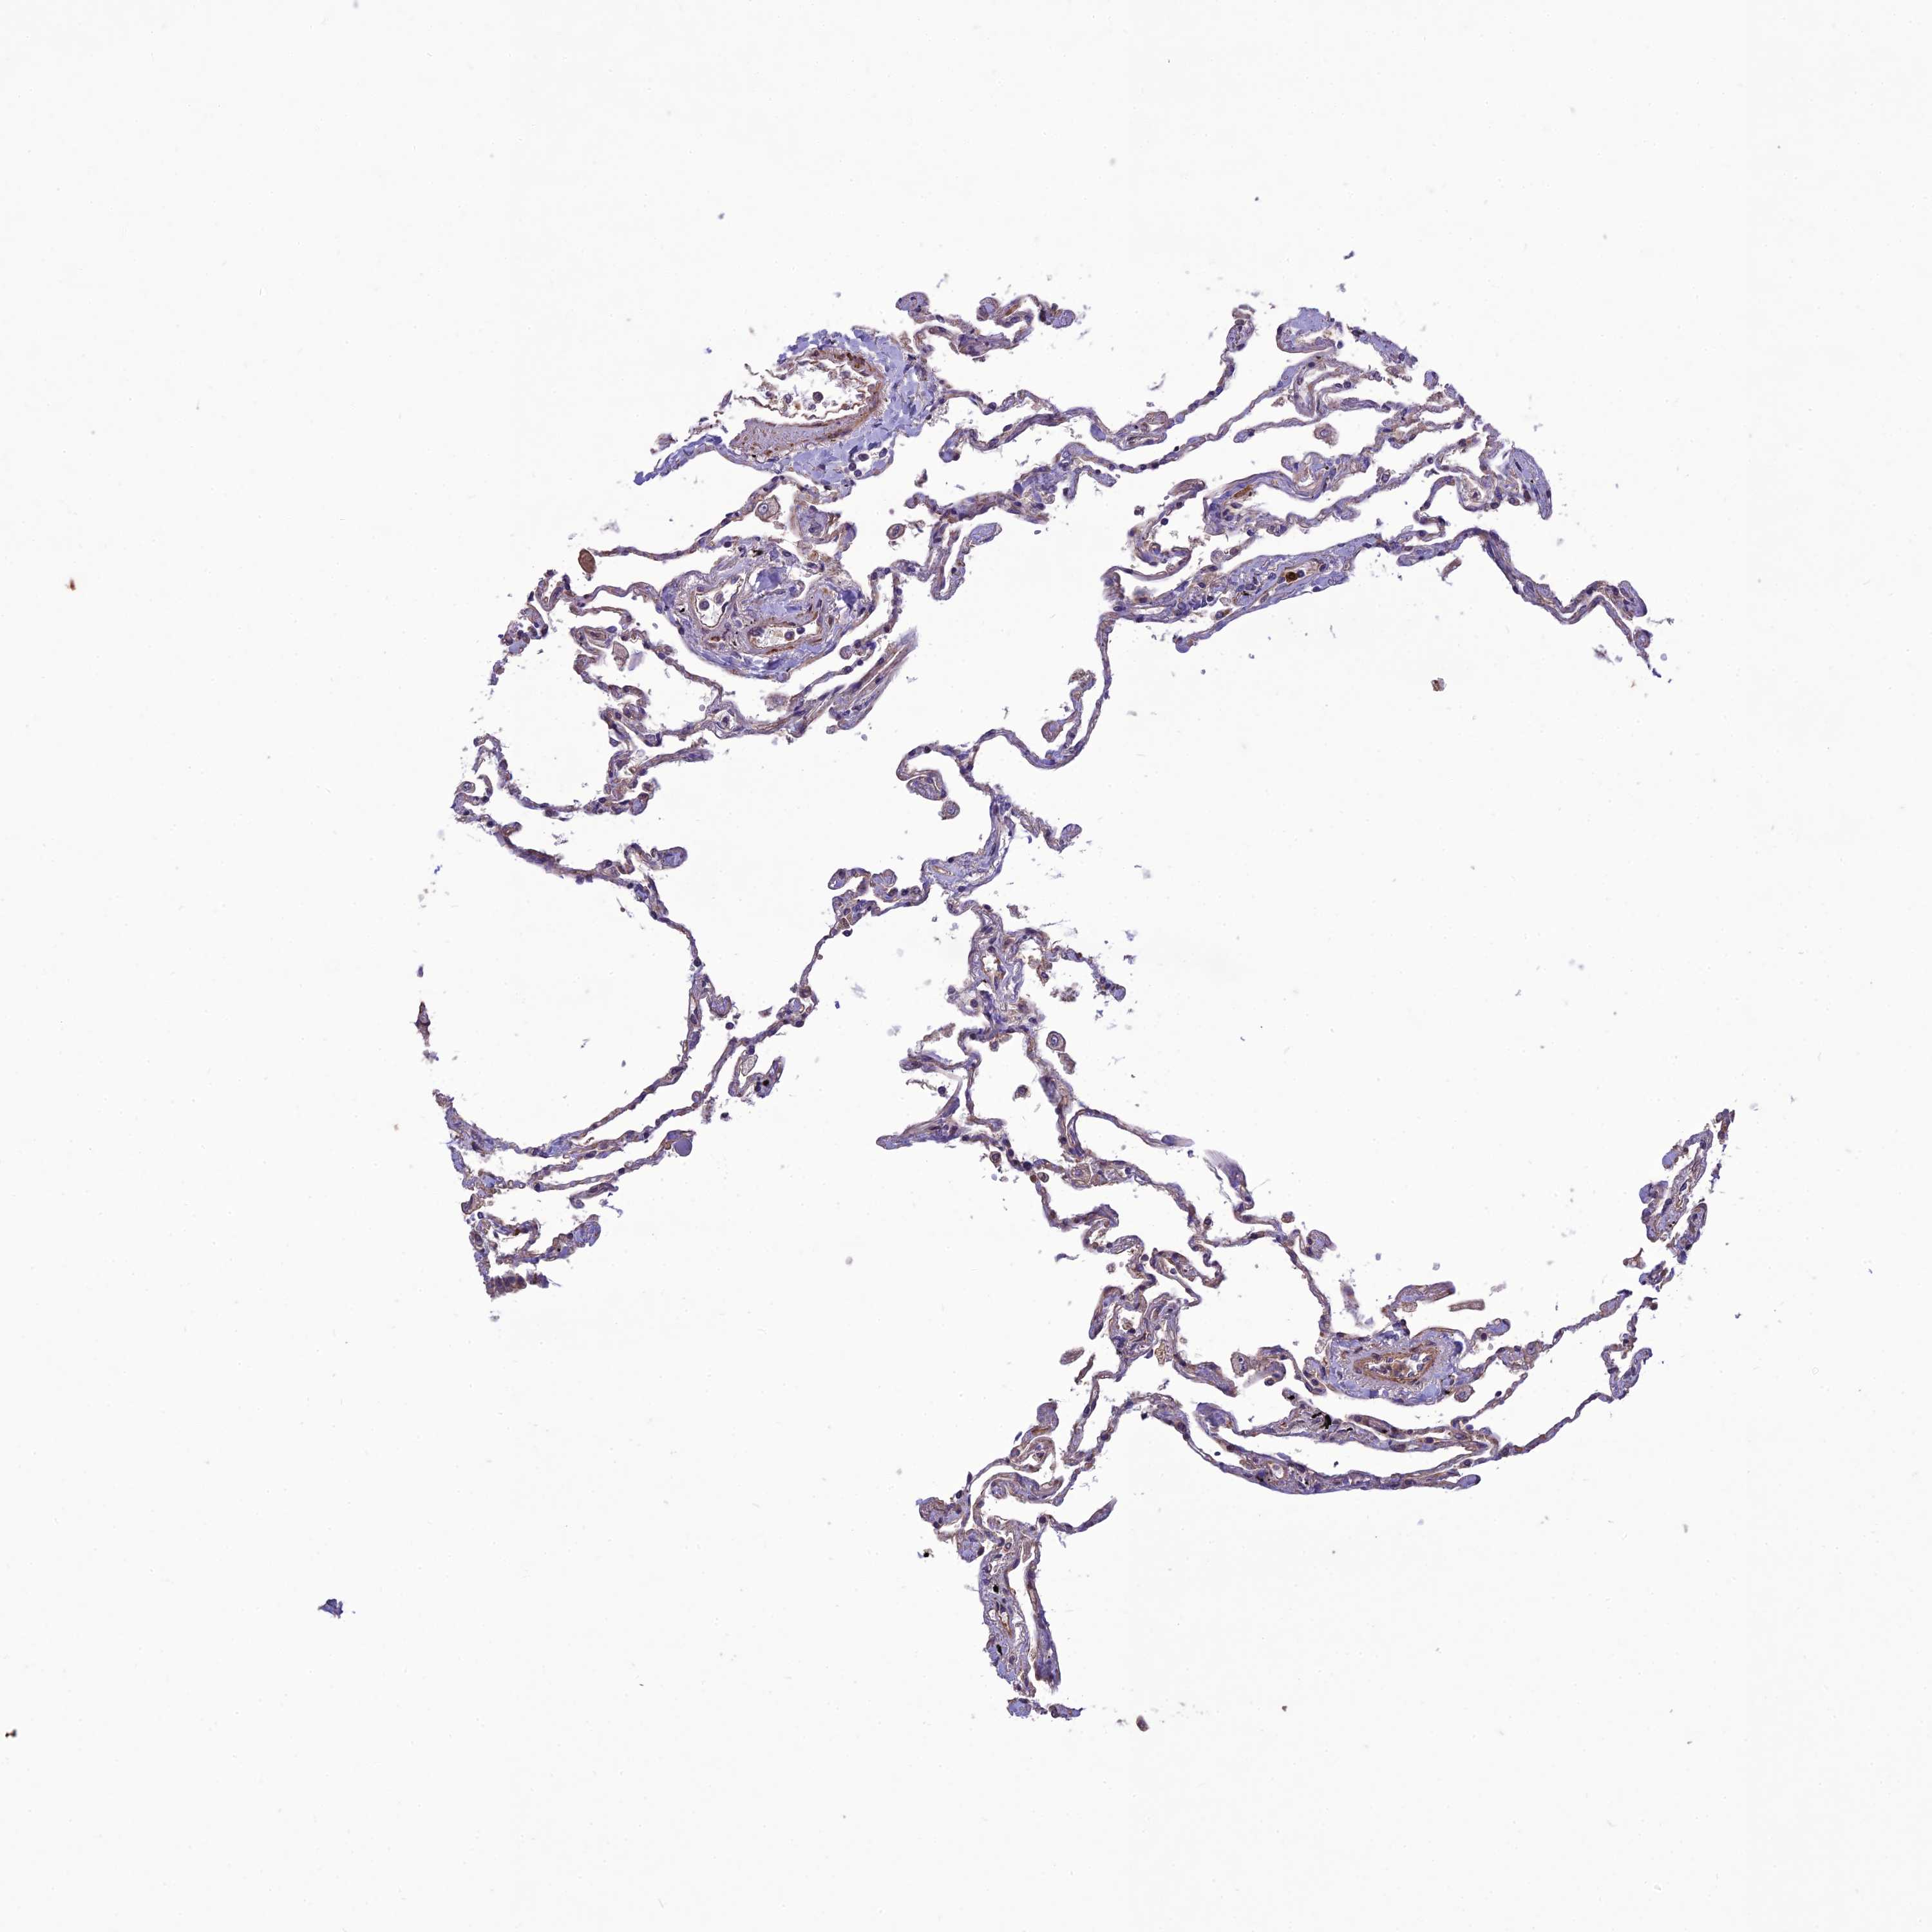

Antibody staining in the annotated cell types in the current human tissue is reported as not detected, low, medium, or high. This score is based on the staining intensity and fraction of stained cells.